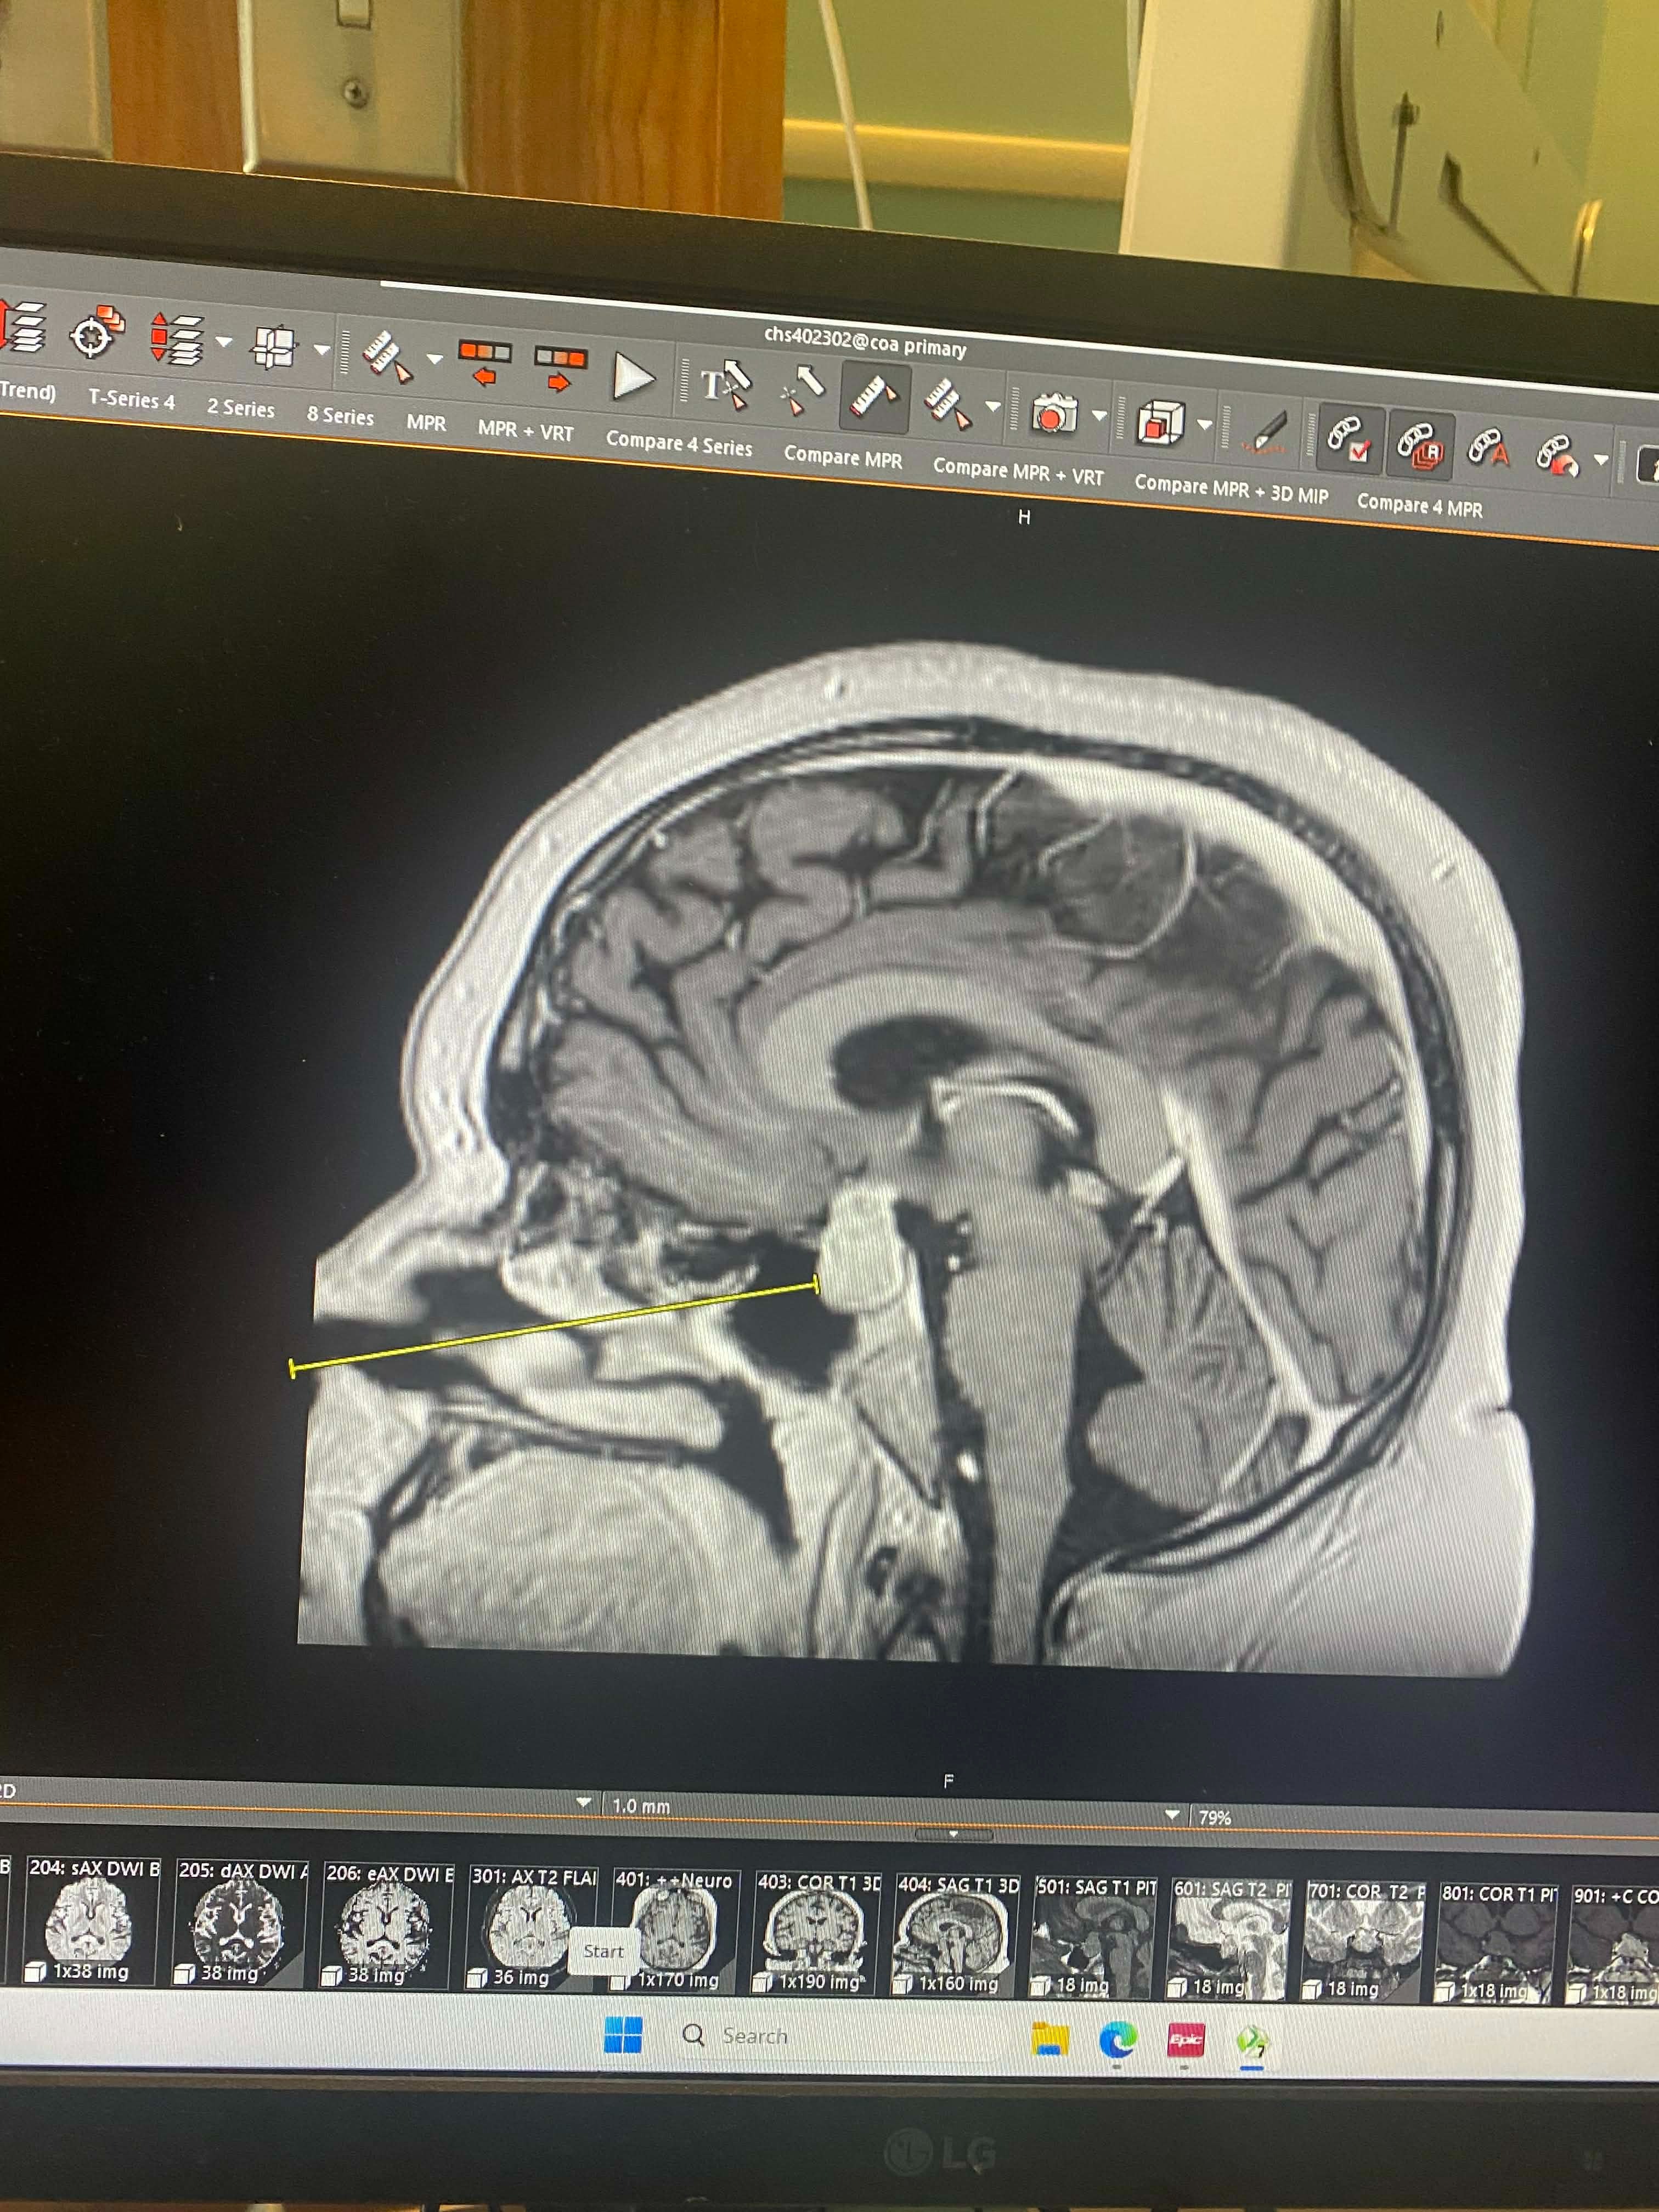

Our 10-year-old daughter, Liz, was diagnosed with Cushing’s Disease, caused by a 25mm tumor on her pituitary gland. She is currently at Children’s Hospital with my wife, preparing for brain surgery and an extended recovery. Our focus right now has to be on keeping her safe, supported, and healing.